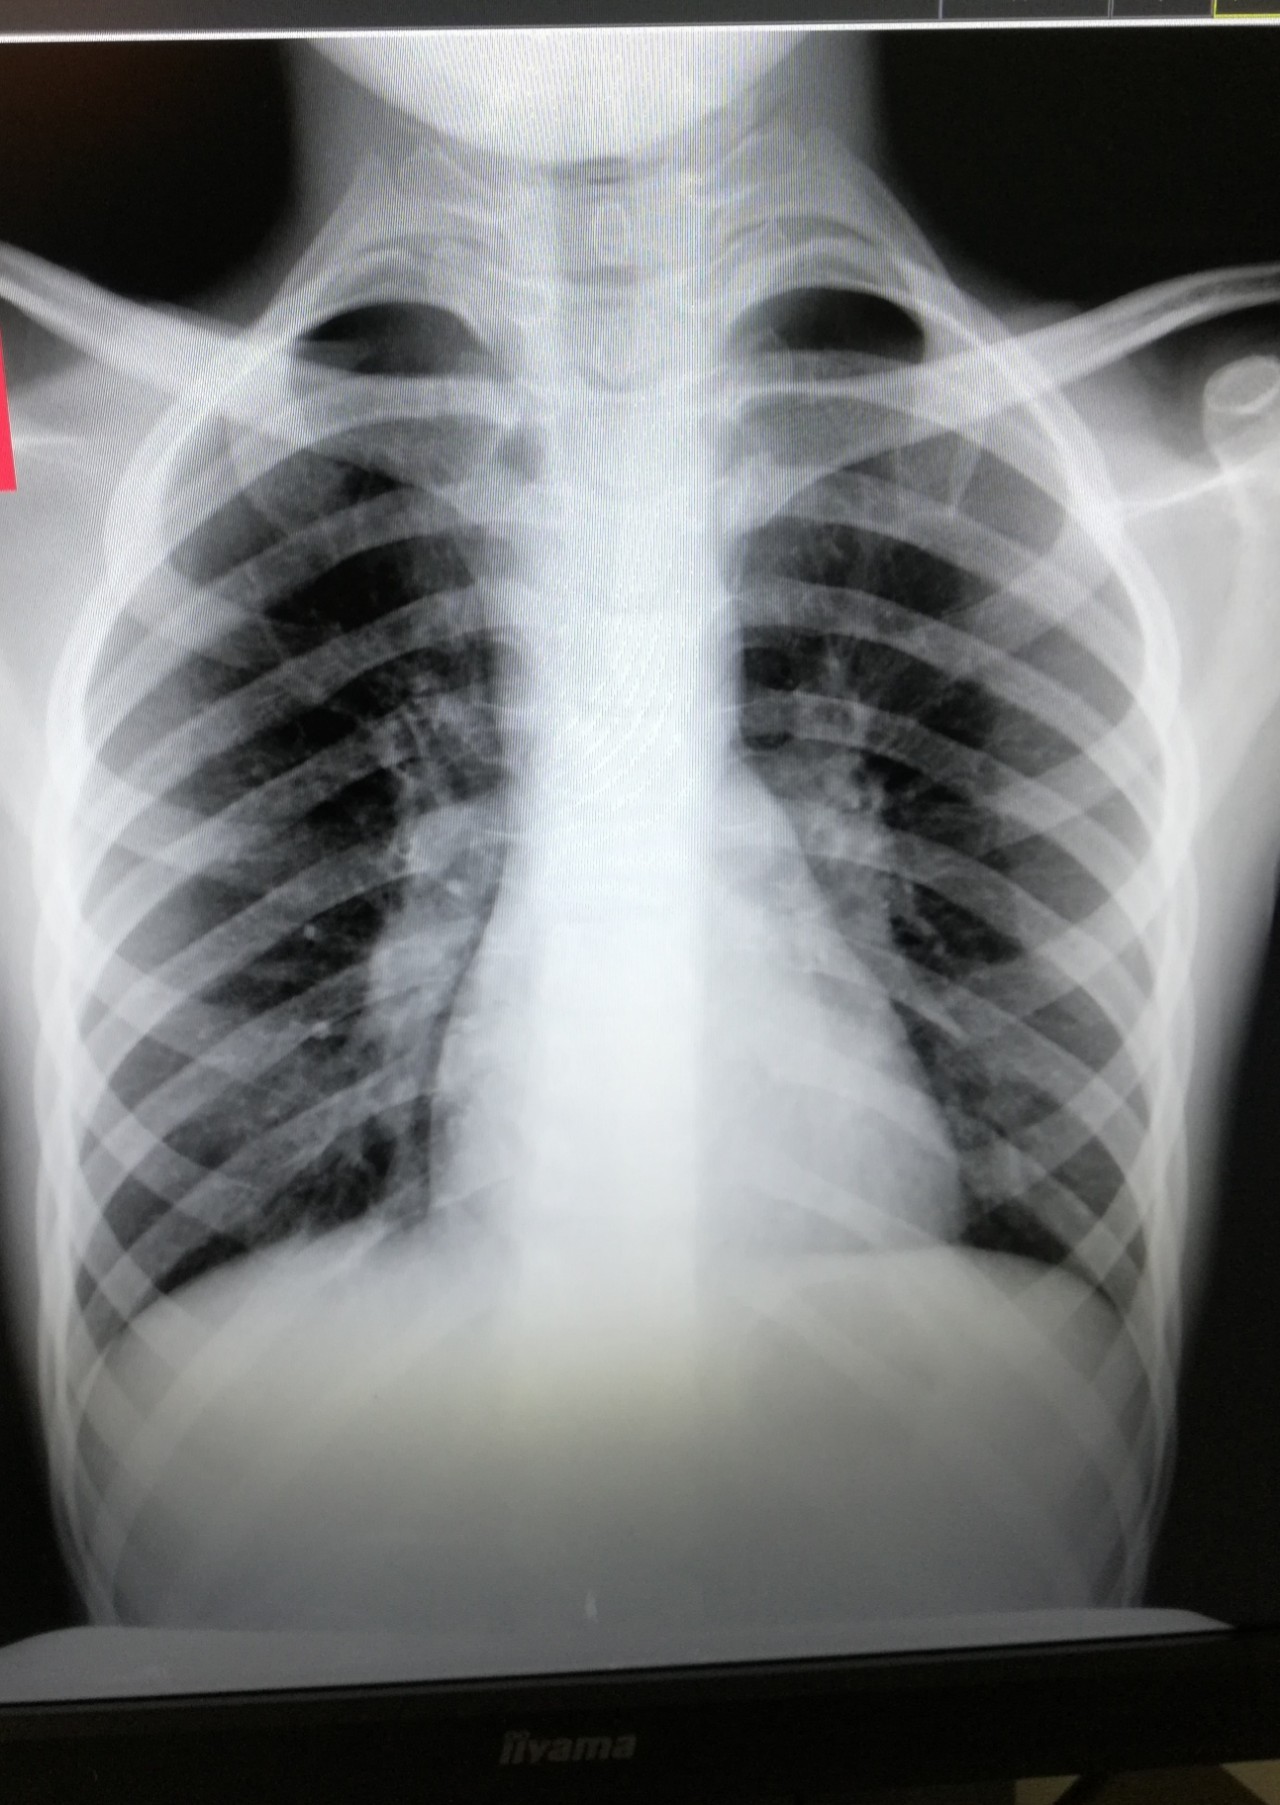

Рентген здоровых легких: примеры снимков и советы

Раздел: Сокровищница опыта